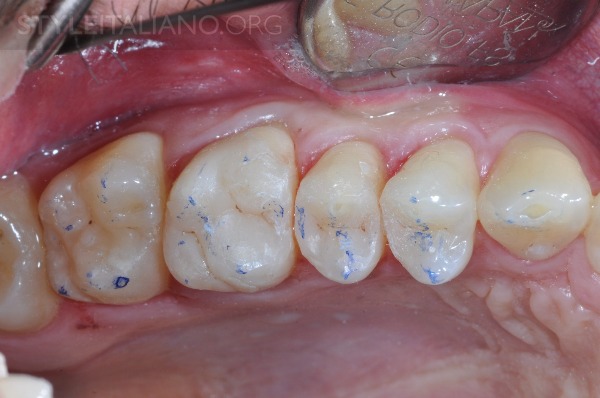

图11 咬合检查:需要一些更正,立即执行。